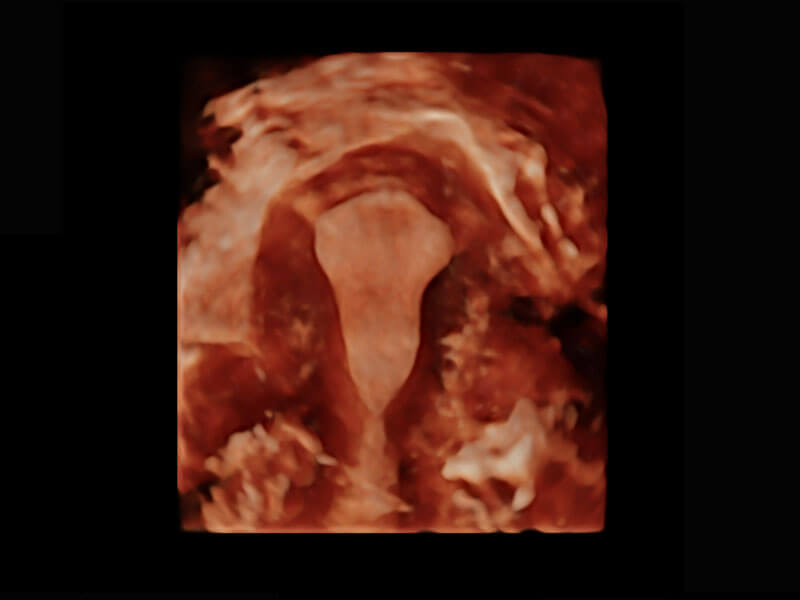

腔内三维-宫内节育器

腔内三维-光影成像

P60搭载一系列胎儿心脏成像技术,实现精细的胎儿心脏评估。

四腔切面

四腔心血流

右室双出口

胎心容积成像